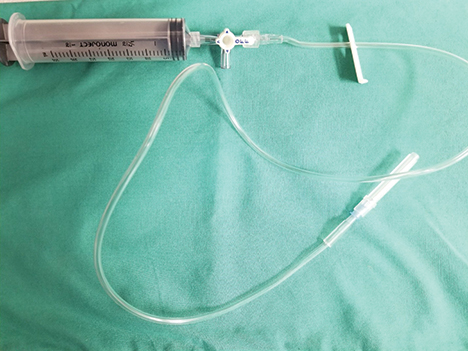

Cystocentesis may also be used therapeutically in patients that have urinary obstruction secondary to uroliths, urethral plugs, and/or neoplasia. Decompressive cystocentesis can alleviate patient discomfort prior to urinary obstruction removal and can lower intraluminal bladder pressure and facilitate retropulsion of urethral plugs/uroliths, potentially easing catheterization.7 Decompressive cystocentesis should be performed with an extension set and a 3-way stopcock to allow for a single needle insertion as opposed to multiple needle insertions. Although decompressive cystocentesis has previously been discouraged, studies have suggested there is minimal risk for bladder rupture/uroperitoneum.8